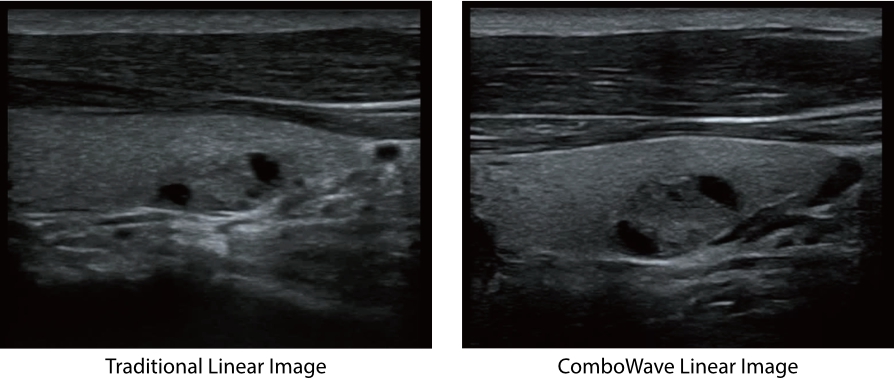

ComboWave

Im Vergleich zu herk?mmlichen Linear-Schallk?pfen verwenden ComboWave-Schallsonden einen piezoelektrischenVerbundwerkstoff. Damit gelingt es, das akustische Spektrum gezielt zu optimieren und die Impedanz zu reduzieren.